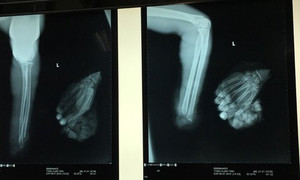

Các bác sĩ Bệnh viện Đa khoa Bình Dương vừa phẫu thuật đưa bàn tay đứt lìa trở lại cánh tay cho thai phụ mang song thai, sau 65 ngày "nuôi" dưới cẳng chân.

Do làm việc bất cẩn, T. bị máy xén giấy cắt lìa bàn tay trái, sau đó được đồng nghiệp sơ cứu, cho tay vào thùng đá đi cấp cứu.